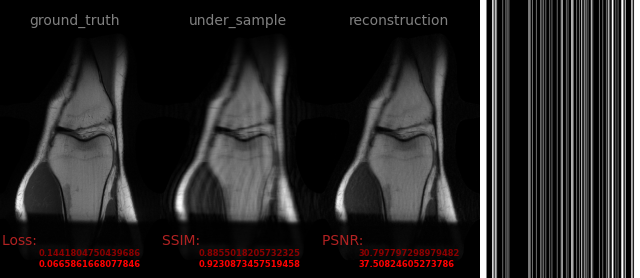

AVS-Net

Image-to-Image

medical